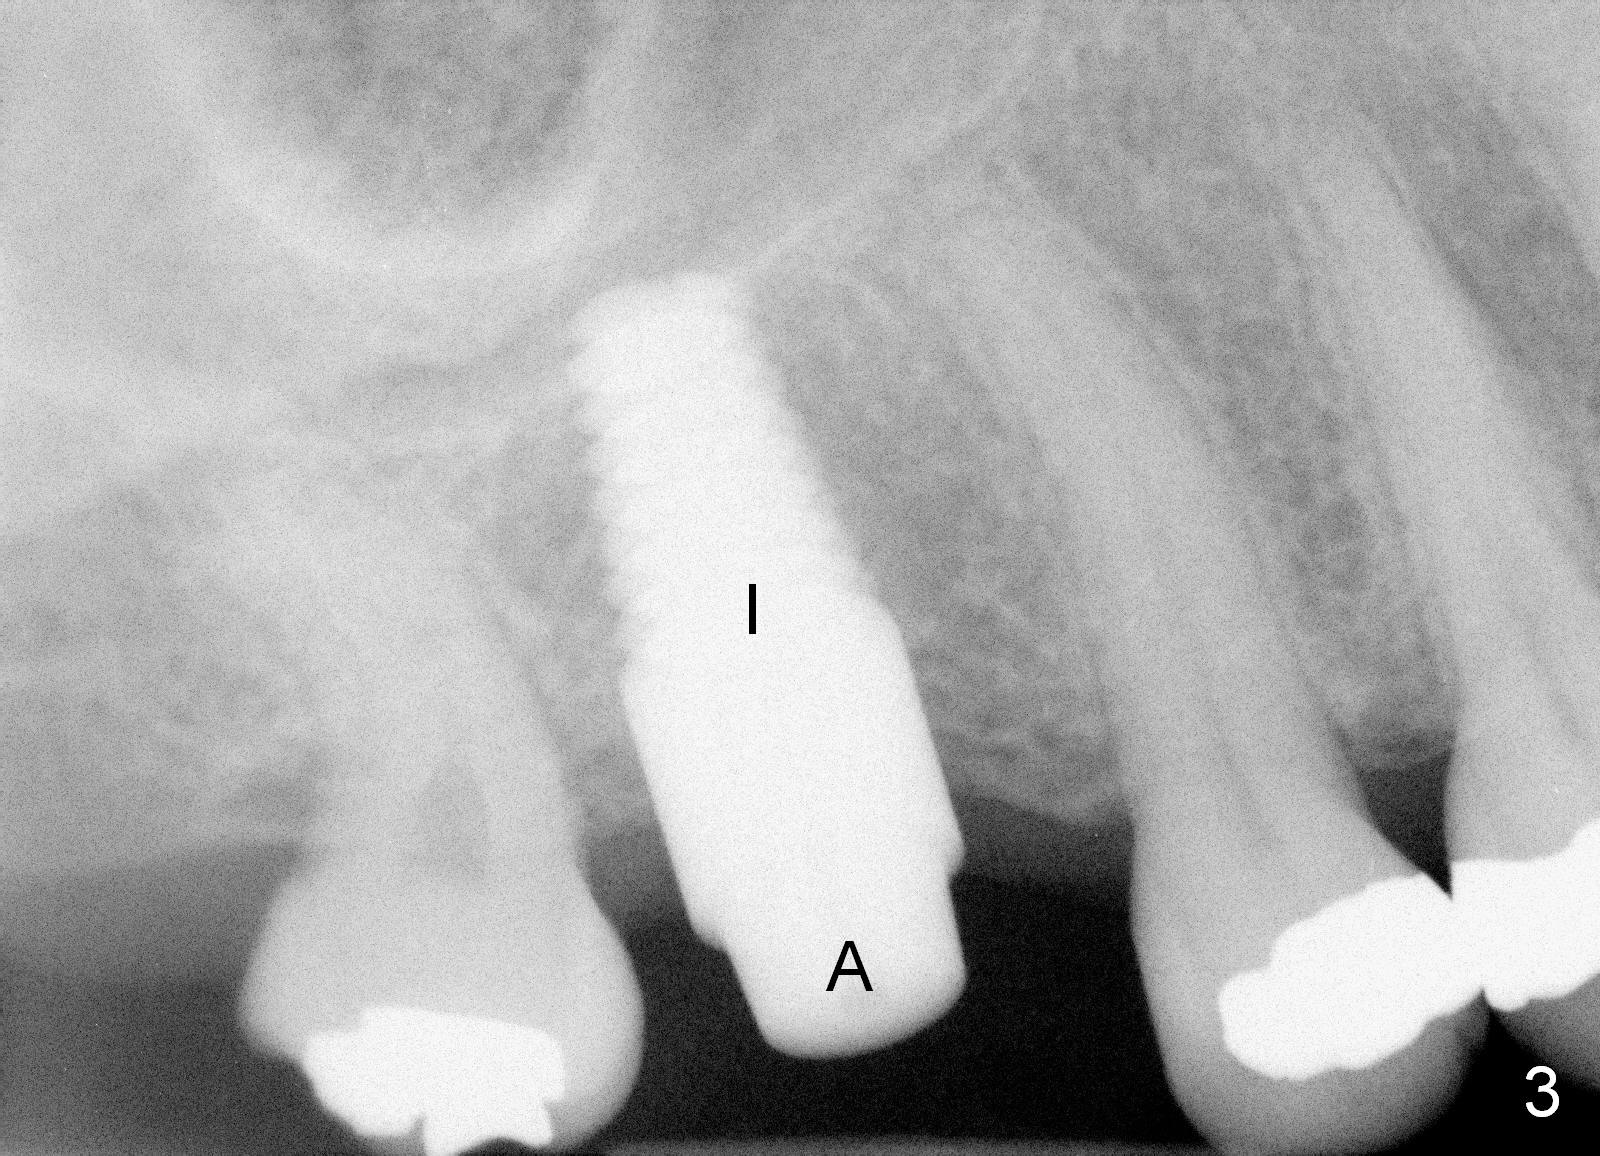

A 50-year-old lady requests implant placement at the site of #3 first. The ridge is mild to moderate atrophy. Immediately preop PA shows bone height ~ 10 mm (Fig.1 green line) and gingiva to sinus floor distance 12 mm (red line). A 10 mm incision is made over the crest. The bone is felt D3, whereas the earlier case D4. Bone expansion and condensation is still performed because it is the least invasive, no drill or suture. In brief the osteotomy is created by osteotomes, followed by taps (4.5-6 mm) (Fig.2: 4.5 mm). A 6x14 mm gingiva-level implant is placed with insertion torque of 60 Ncm (Fig.3 I). A 5x3 mm abutment (A) is placed for an immediate provisional. There is no bone resorption less than 4 months postop (Fig.4). After reprep, impression is taken for final restoration.